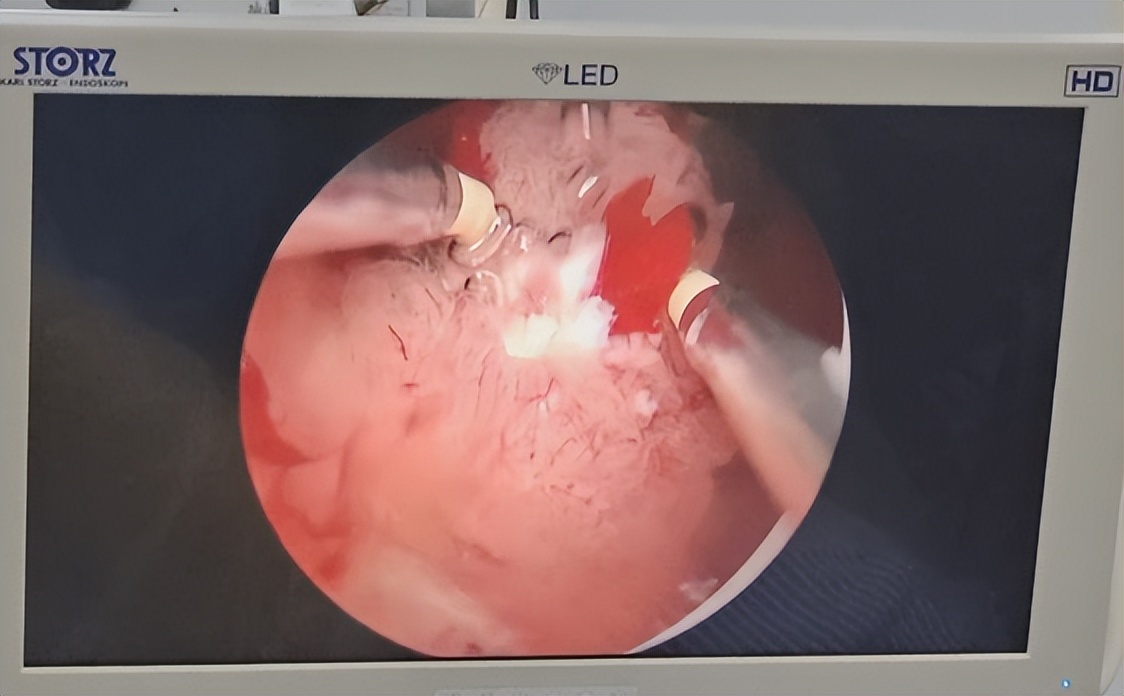

4、膀胱癌的治疗: 以手术治疗为主。根据肿瘤的临床分期、病理并结合病人全身状况,选择合适的手术方式。 原则上Ta 、T 及局限的分化较好的T2 期肿瘤,可采用保留膀胱的手术。T期原则上Ta 、T 及局限的分化较好的T2 期肿瘤,可采用保留膀胱的手术。a、T1: 期肿瘤,以经尿道膀胱肿瘤切 除术(常称电切手术 )为主要治疗方法。如无电切设备,可作膀胱开放手术。为预防肿瘤复发,术后可采用膀胱内药物灌 注治疗。